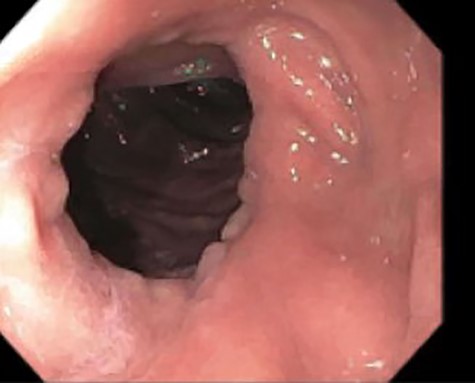

A 46-year-old woman with a body mass index of 43 and a past surgical history of Roux-en-Y gastric bypass 6 years prior presented to the bariatrics clinic with a chief complaint of weight gain of over 30 pounds over a few months. An upper GI series was suspicious for a fistula between the gastric pouch and gastric remnant. The patient was referred to gastroenterology for upper endoscopy. Endoscopy was uneventful and detected no abnormalities. The gastro-jejunal anastomosis had an adequate caliber (Fig. 1), and there was no evidence of gastric fistula (Fig. 2).

Esophagogastroduodenoscopy (EGD)–gastrojejunostomy, staple line, with no abnormal findings.